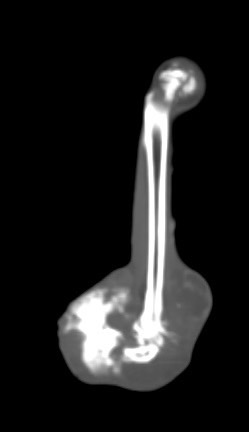

卵巢殘留

卵巢殘留是指雌性動物在進行絕育手術後,仍然有部分卵巢組織殘留,進而導致術後仍然反覆發情,並可能繼發子宮殘端蓄膿、乳腺腫瘤等疾病。而殘存的卵巢,由於體積小且子宮角已被摘除,往往難以找尋。幸而隨著動物醫療進步,依靠電腦斷層、內視鏡等先進設備,卵巢殘留的情況已不再難以處理。

小花是一隻一歲多的母貓,半年前曾在其他醫院做過絕育手術,但手術當下卻只找到單側的子宮卵巢,且在這半年當中仍然反反覆覆地發情,讓飼主十分擔心,於是來到築心尋求治療。在了解小花的狀況後,我們為小花安排了電腦斷層掃描,並在腹腔的左側發現了疑似殘存的卵巢影像(見圖示),接著,在影像定位的協助下順利開腹取出殘存的卵巢和發育異常子宮角,而在殘存的子宮內已然形成了子宮蓄膿。

幸虧子宮蓄膿的情形尚不嚴重,並沒有造成感染範圍的擴散,手術後經過一小段時間的修養,小花目前已經順利拆線,在家過著無憂無慮的生活囉。